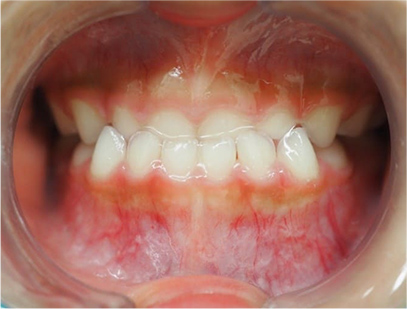

前歯の反対咬合

前歯部の反対咬合を主訴として来院されました。精査、診断の結果「前歯部の反対咬合」と診断されました。

上顎に取り外しのできる教師装置を使用して裏側から前歯を前方に拡大します。 使用は、お家の中で食事の時と歯ブラシの時以外は使用することを指示しました。

取り外しのできる矯正装置

治療期間は患者様の努力とお母さまの協力が得られて5か月間で終了しました。